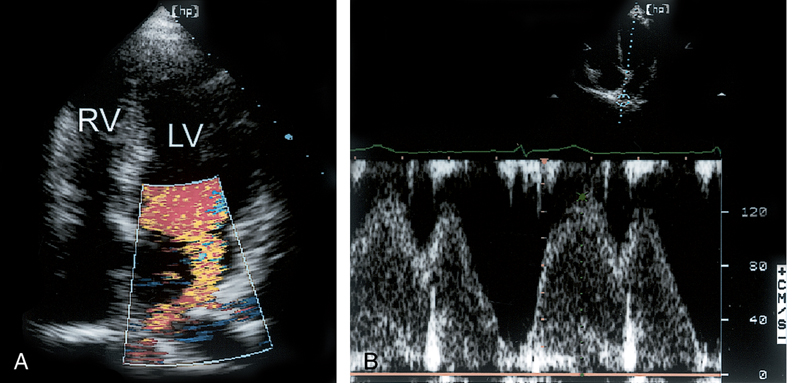

فحوصات تشخيصية لبعض امراض القلب والشرايين التاجية